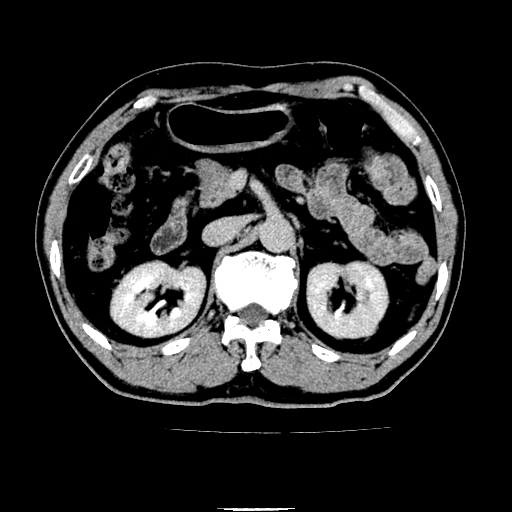

以下是引用chenqiong在2010-3-25 20:56:00的发言:[br]1、胆囊炎,胆囊息肉[br]2、肝内胆管及胆总管扩张,胆总管下端结石[br]3、十二指肠乳头旁憩室

以下是引用zxl51642在2010-3-26 10:47:00的发言:[br]胆囊炎,胆囊息肉,胆总管扩张,但未看到明显肿块,肝内胆管扩张不像恶性,炎性狭窄或阴性结石可能吧,建议mrcp,右肾小囊肿